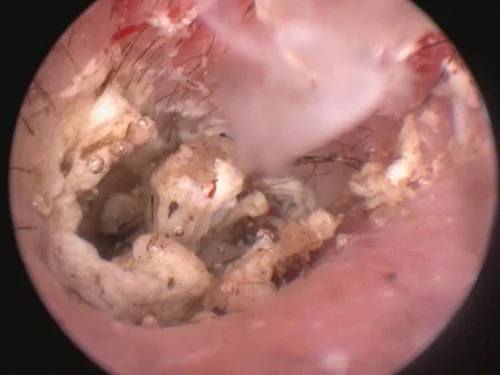

Ear disease often recurs and persists in dogs due to incomplete or ineffective treatments or failure to diagnose the underlying cause. To improve the treatment of pets with chronic ear disease, our experienced veterinarians often utilize video otoscopy.

Video otoscopy has revolutionized the treatment of ear infections by our medical team as it provides amazing clarity to assess the condition of the ear canal, eardrum, and, at times, the middle ear.

Video otoscopy is the use of a small rigid otoscope with a camera built in that can be passed into the ear canal. The image is then projected onto a screen allowing magnification and much greater clarity to observe the deeper ear canal and structures.

Small channels within the otoscope also allow instruments to be passed into the ear canal to facilitate deeper cleaning, polyp or tumor removal, and other procedures. The use of video otoscopy in a challenging ear case is often the difference between months of continued struggles and a much more rapid resolution of infection and disease.